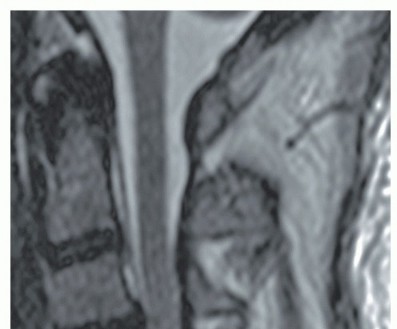

IMAGING AND OTHER DIAGNOSTIC STUDIES A lateral radiographic view can be helpful in showing the amount of congenital cervical stenosis as well as sagittal alignment. Lateral views are consistent with congenital stenosis when the ratio of the diameter of the canal to the diameter of the vertebral body is less than 0.8. Particularly if OPLL is suspected, computed tomography (CT) scans (with or without myelograms, depending on whether a high-quality magnetic resonance imaging [MRI] is available) are helpful in delineating bony versus soft tissue pathology. ## DIFFERENTIAL DIAGNOSIS Of cervical myelopathy Amyotrophic lateral sclerosis Myopathies Peripheral neuropathy Syringomyelia Multiple sclerosis Diabetic neuropathy Brachial plexopathy ## NONOPERATIVE MANAGEMENT Surgery is generally the treatment of choice for symptomatic cervical myelopathy. Nonoperative treatment of cervical myelopathy is typically reserved for patients who cannot tolerate surgery.4 Controversy exists regarding the management of patients with asymptomatic spinal cord compression. In those with severe asymptomatic compression, consideration should be given to prophylactic surgery, particularly if cord signal changes are present, to prevent spinal cord injury with trauma (eg, central cord syndrome) (FIG 2).

### FIG 2 • Sagittal T2-weighted MRI demonstrating spinal cord signal changes.